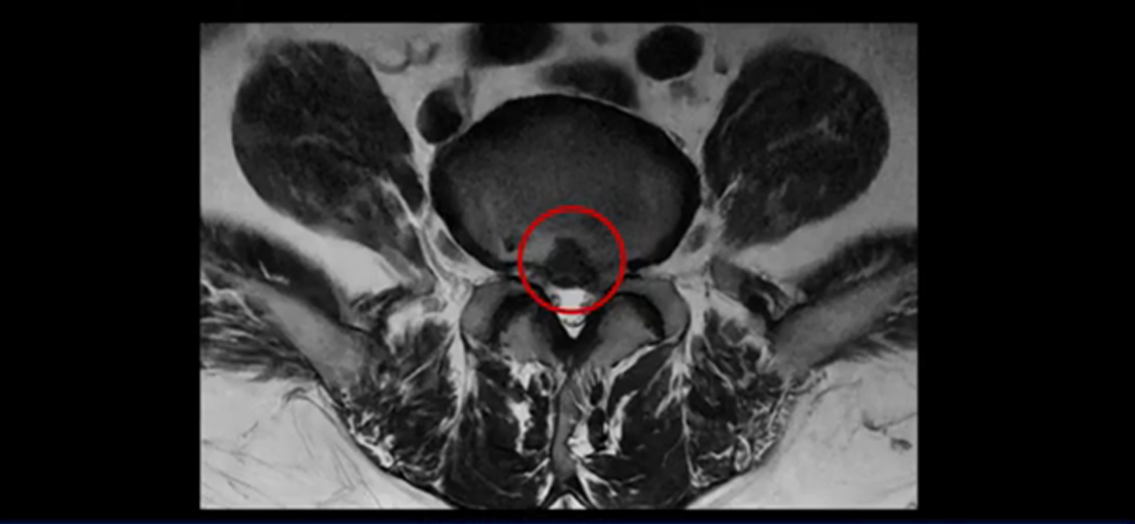

가운데로 심하게 밀려 나와 있는데요.

또 4번 5번에는 협착으로 척추관이 많이 좁아져 있습니다.